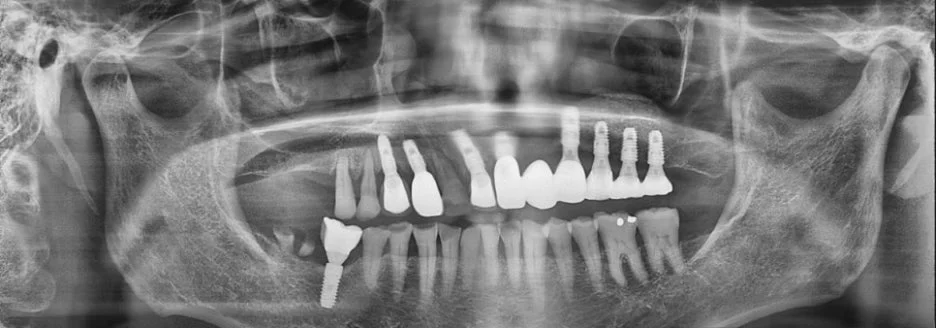

먼저 불편함이 있던 왼쪽 앞니 임플란트를 우선 진행하셨고, 전체 치조골의 80% 이상이 인공뼈로 채워지는 넓은 범위의 치조골 이식술도 함께 시행하였습니다.

몇 년이 지난 뒤, 이번에는 오른쪽 치료를 원하셔서 다시 내원하셨습니다.

임플란트의 상부 톱니 부분이 골 속에서 안정적으로 자리 잡고 있는 것을 확인할 수 있었고, 뼈이식 부위 역시 잘 유지되고 있었습니다.